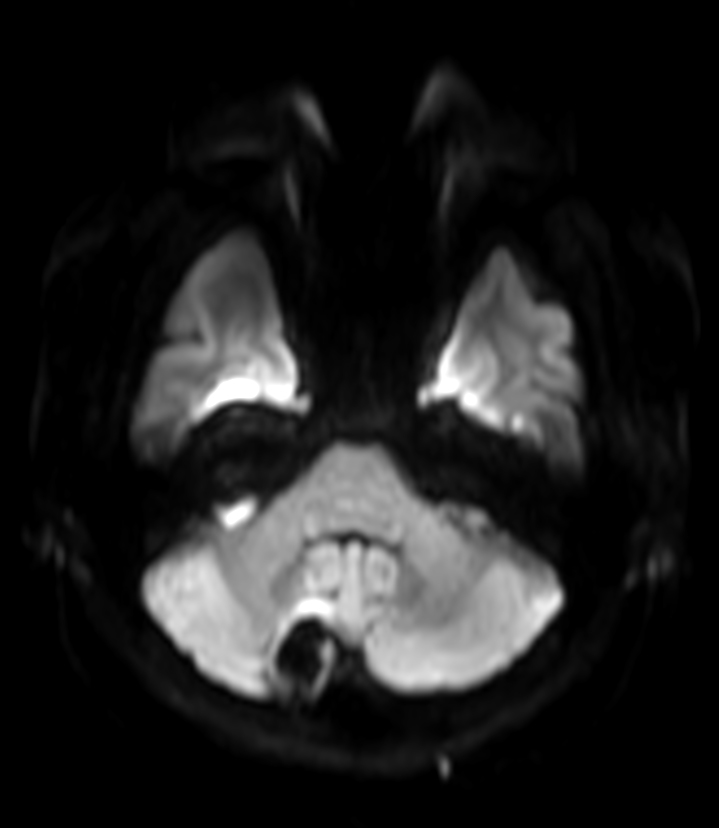

Patient with a lesion in the cerebellum. The ExamCard includes Compressed SENSE to accelerate the entire exam and techniques for motion reduced imaging (MultiVane XD), 3D imaging to acquire high resolution data in multiple directions, 3D susceptibility weighted imaging (SWIp), angiography sequences (Time-of-Flight and Contrast-Enhanced MRA with both arterial and venous phases), DTI with MultiBand SENSE to acquire a high number of diffusion directions in a short scan time and EPIC Brain to bring down any residual distortion.

DWI b1000